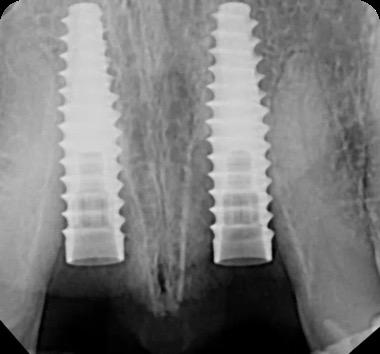

BioHorizons has introduced a new implant system that combines the advanced thread design of the Tapered Pro with the precision and stability of the Conelog conical connection. This integration delivers enhanced surgical handling, improved primary stability, and long-term biological benefits, supporting better patient outcomes in both aesthetic and functional zones.

This case was performed by Dr Homa Zadeh, DDS, PhD, a respected leader in periodontology and implant dentistry. Dr Zadeh’s approach emphasizes biologically driven protocols and evidence-based techniques, making this case a strong example of clinical excellence using the Tapered Pro Conical system. It involves the replacement of two front anterior teeth after they fractured off and the full restoration process.

Fig 2. Intraoral radiograph indicating tooth structural loss extent.

Fig 4. Alveolar bone imaging. The alveolar bone was intact, and the alveolar crest was approximately 4mm apical to the restorative margin.

Fig 6. BioHorizons Tapered Pro Conical implants of 3.8 x 15mm placed according to the plan.

Fig 7. Implants immediately after installation.